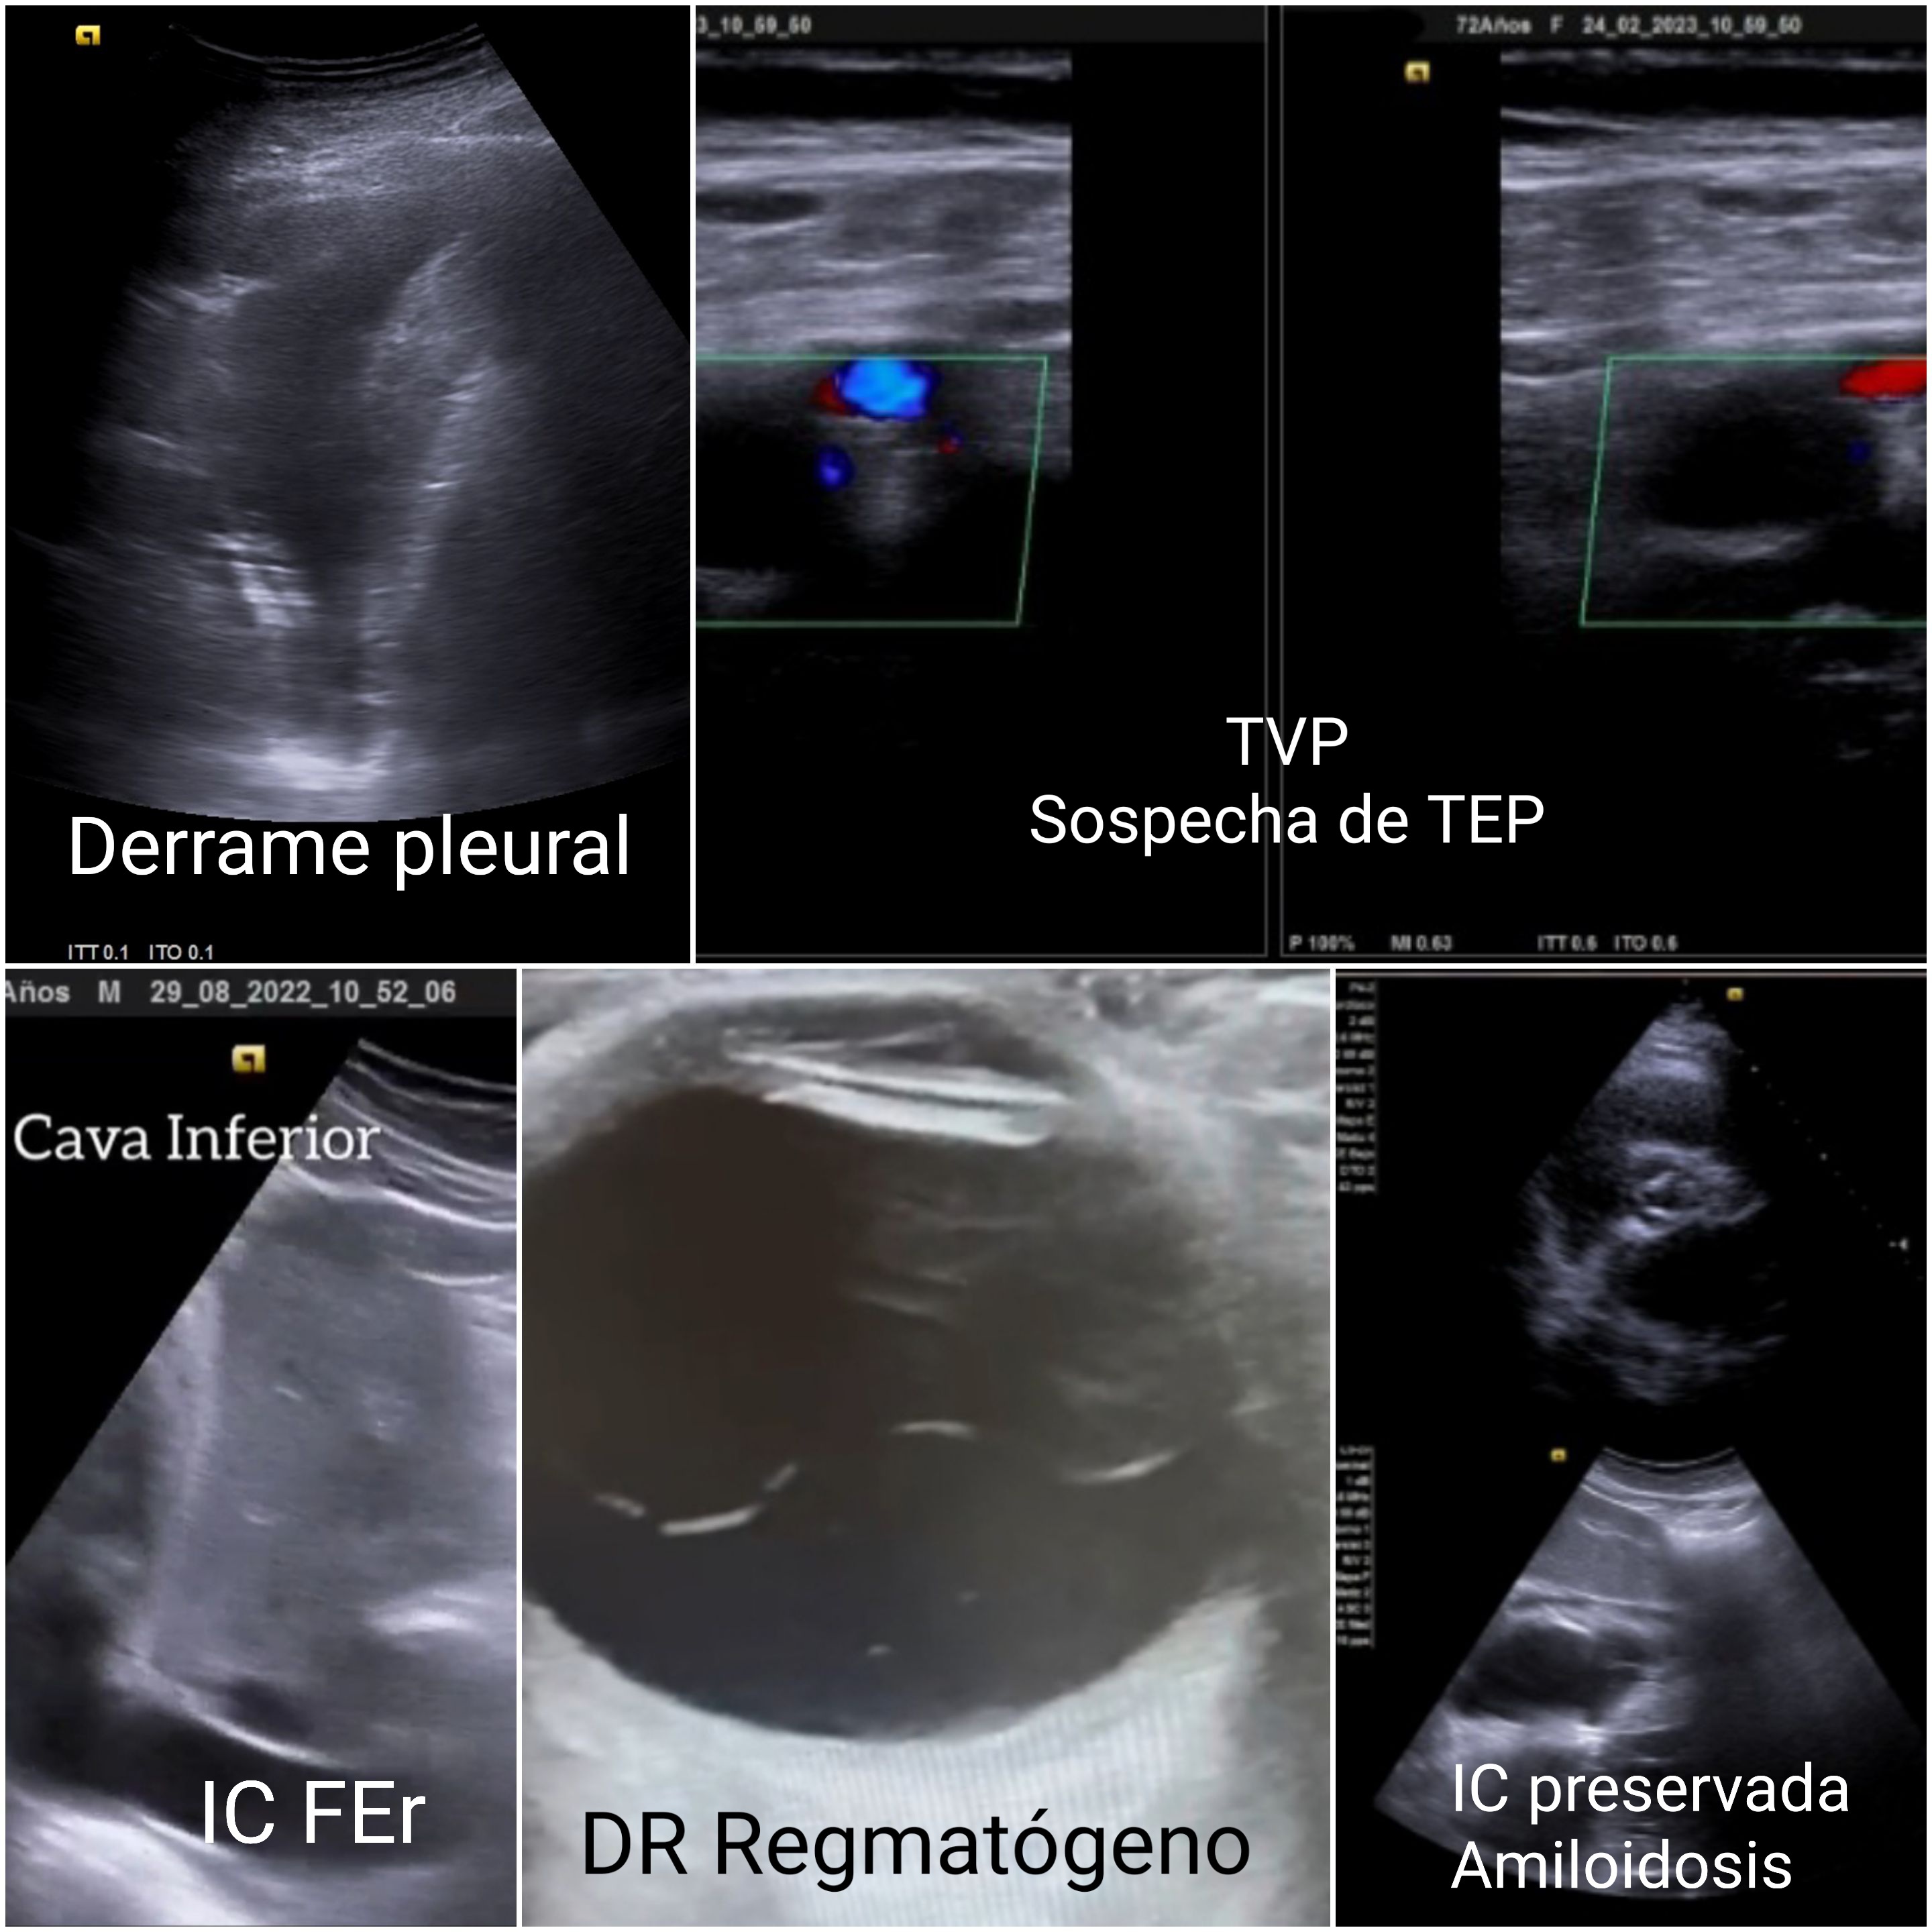

Se presentan 12–15 casos ilustrativos: (1) rotura de cuerdas mitrales recuperada desde lista de espera (ecocardioscopia); (2) postcirugía cardíaca dado de alta con derrame y congestión no detectados; (3) insuficiencia cardíaca (IC) tras pancreatitis con derrame pleural; (4) IC dada de alta pendiente de ecocardiografía, en AP se confirma FE reducida; (5) Trombosis venosa (TV) con disnea sin sin angio-TC; (6) ELA: fasciculaciones por ecografía con alta demora para neurología; (7) desprendimiento de retina reenviado dos veces a urgencias Hospital; (8) aumento del diámetro de la vaina del nervio óptico con sospecha de patología de nervio óptico; (9) lesión de Hill-Sachs no detectada en hospital; (10) lesión renal Bosniak IV (carcinoma renal); (11) tumor vesical de pared tras ecografía hospitalaria previa normal; (12) angioleiomioma etiquetado como quiste epidérmico.